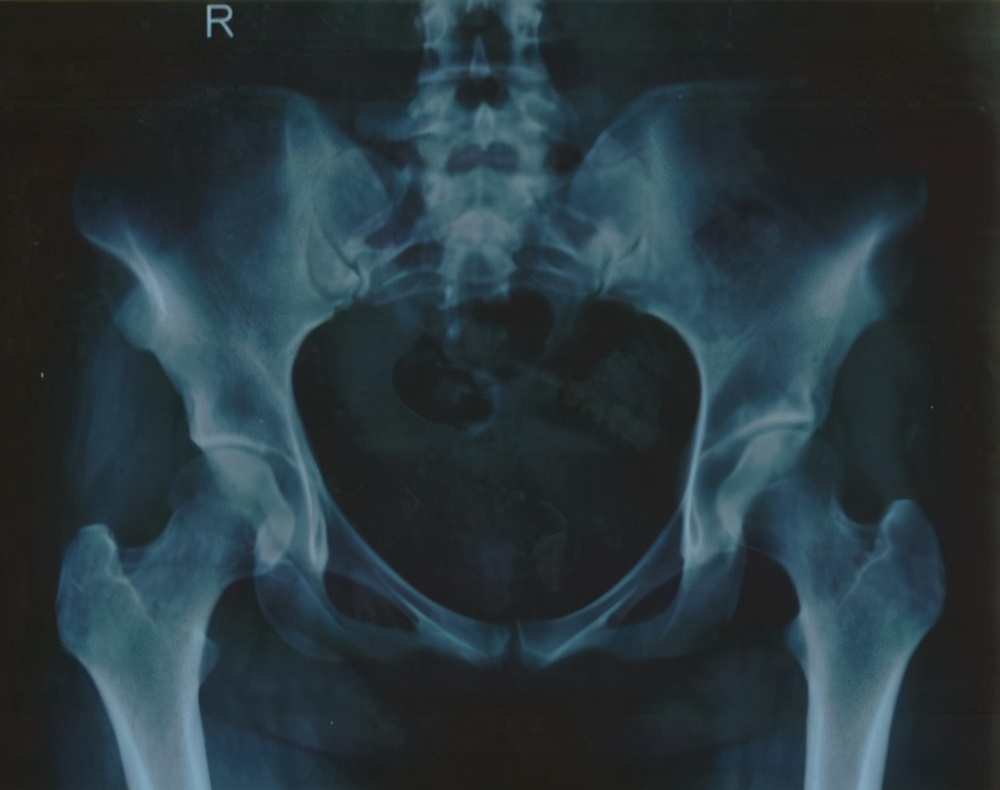

继发甲状旁腺机能亢进症的影像学变化包括:内骨、骨皮质和骨膜的骨吸收、指末趾骨腐蚀、囊肿形成和骨硬化。在这些变化中,骨膜吸收是最常见的影像学改变,主要发生在指骨,还有骨表面、锁骨远端和肋骨,尺骨,胫骨,下颌表面。

骨质硬化的影像学变化导致骨密度增加,而干骺端和软骨病变的诊断则依赖于椎体、骨盆、肋骨、锁骨和各种长骨。仅有的影像学检查显示骨束松动和假骨折,这通常降低了骨密度,但不足以诊断骨软化。放射学检查发现骨密度降低,常用于患有长期肾衰竭的病人。